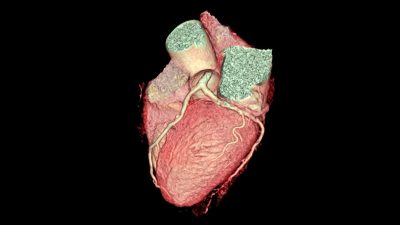

Synopsis: The 10-year follow-up of the SCOT-HEART Study of new-onset chest pain patients randomized to standard care vs. the addition of coronary computed tomography angiography (CTA) has shown that coronary heart disease-related death, myocardial infarction, and other adverse cardiovascular outcomes are reduced with CTA use, perhaps because preventive therapy is increased.

The five-year follow-up results of the Scottish Computed Tomography of the Heart (SCOT-HEART) trial in patients presenting with new-onset chest pain demonstrated that the combined primary endpoint of coronary heart disease (CHD) mortality and nonfatal myocardial infarction (MI) was significantly reduced in the group that received computed tomography angiography (CTA) to guide therapy compared to those who received standard care, without increasing invasive coronary procedures or revascularization. However, since CHD is a progressive disease, there was concern that these results would attenuate over time as the patients aged. Thus, this prespecified 10-year analysis of SCOT-HEART is of interest.

Median CT coronary artery calcium score in the patients was 20 Agatston units (range 0-230). CTA exhibited 37% of patients with normal coronary arteries, 38% of patients with nonobstructive CHD, and 24% of patients with obstructive CHD. Ten-year follow-up data were available in 96% of patients. The primary outcome was less frequent in patients in the CTA group (6.6 vs. 8.2%; hazard ratio [HR], 0.79; 95% confidence interval [CI], 0.63-0.99; P = 0.044).